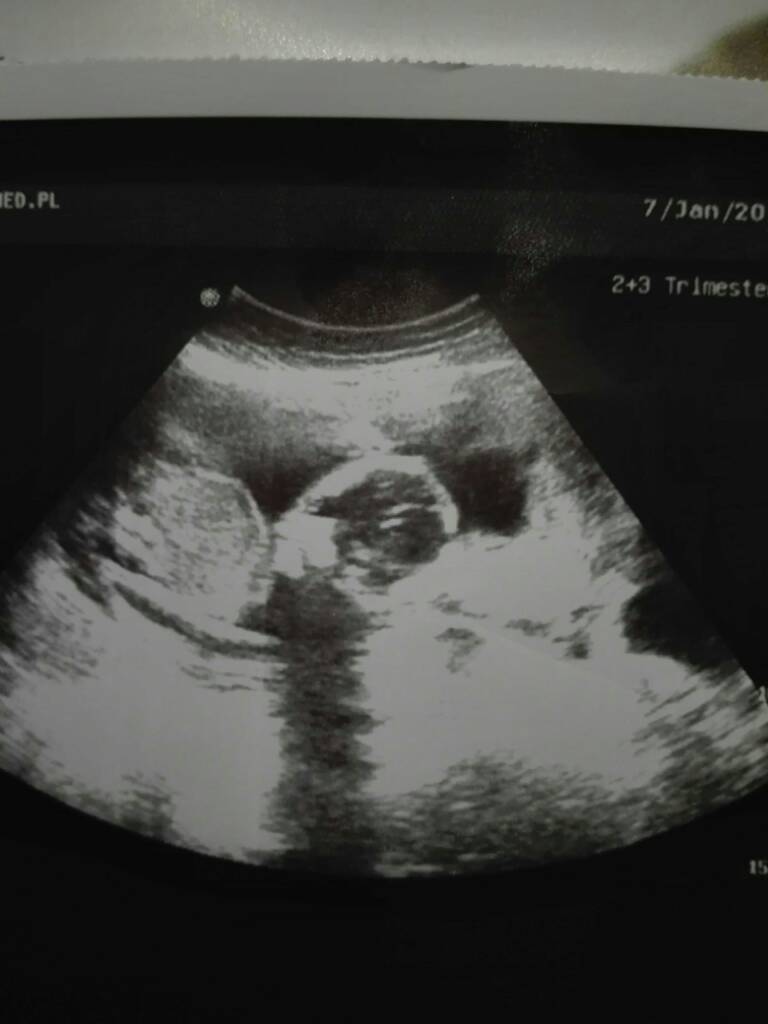

A tak oglonie reszta ok, dzidzia ma juz 16,4cm i wazy 260g [emoji7] no i doktorek nie potwierdził mi dzis corki bo teraz juz sam nie byl pewny [emoji52]

IMG_20190107_194501.jpeg